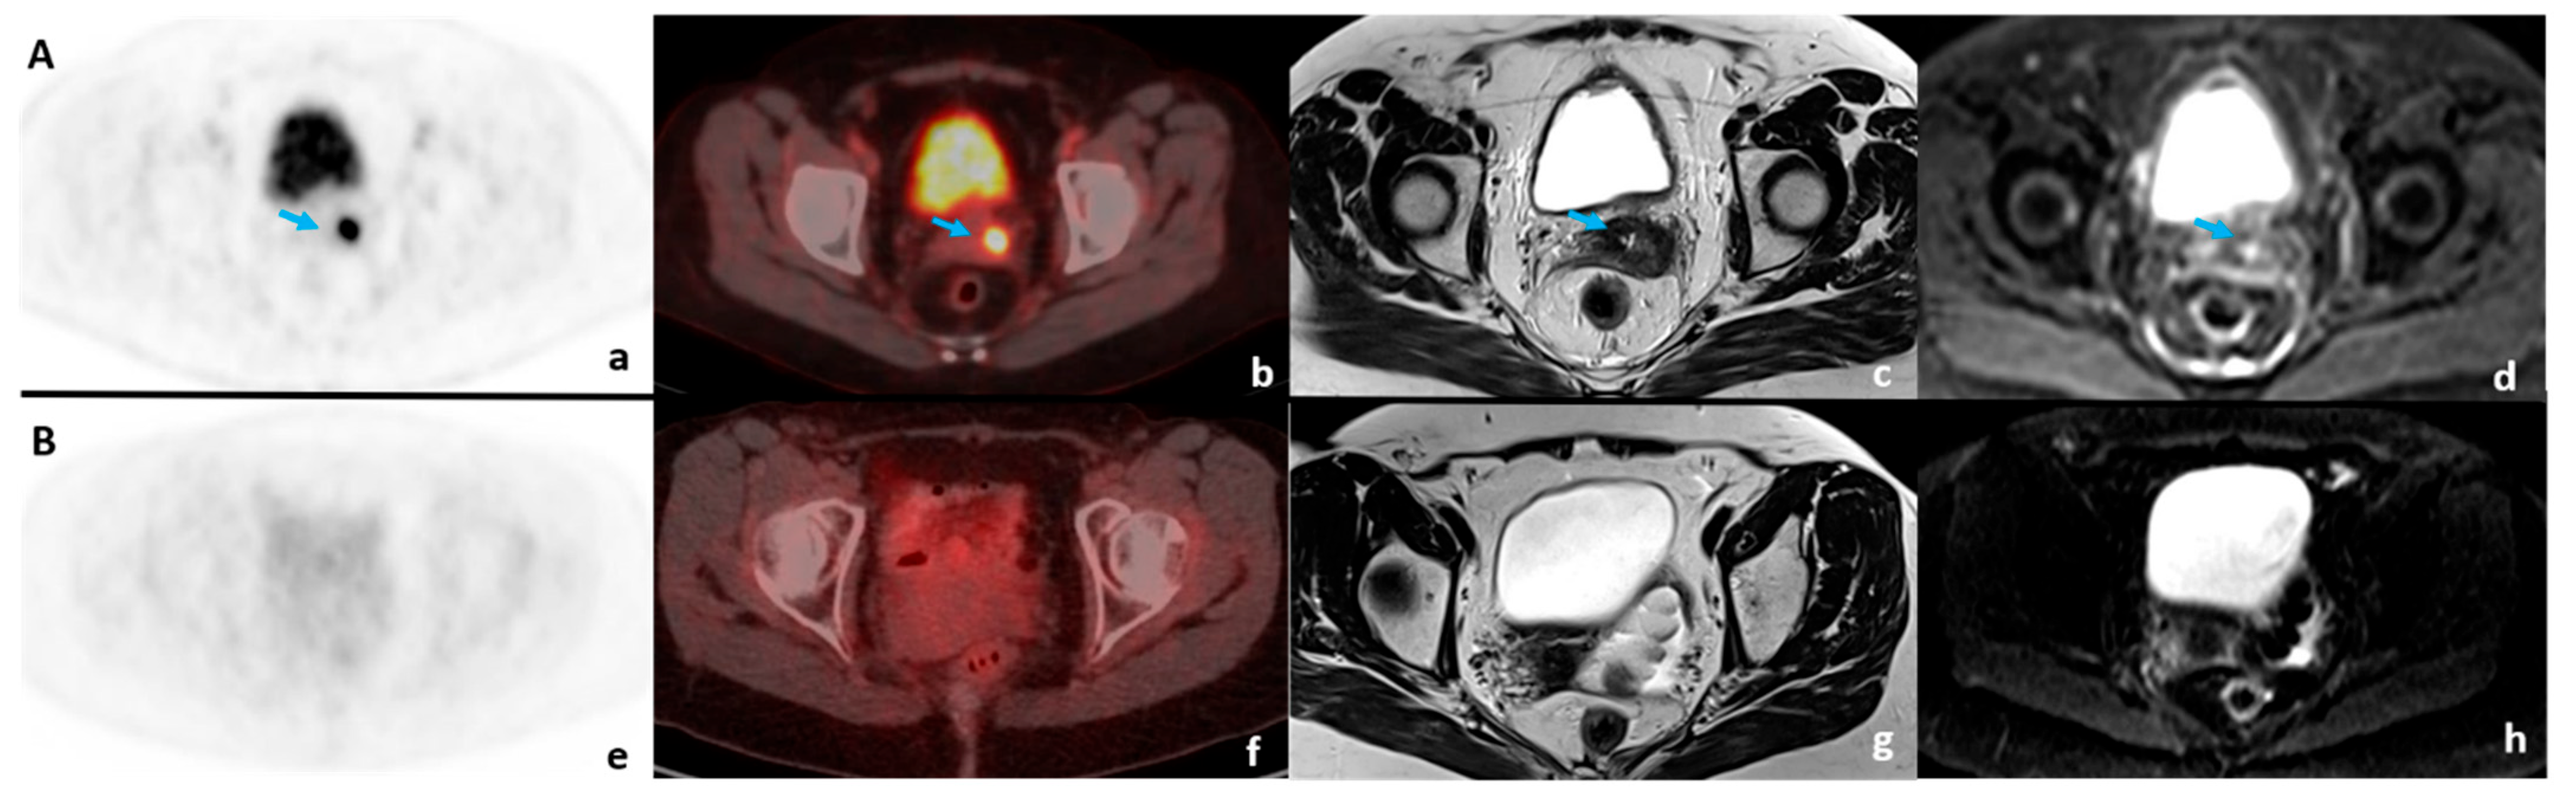

- Perrone, A.M.; Dondi, G.; Coe, M.; Ferioli, M.; Telo, S.; Galuppi, A.; De Crescenzo, E.; Tesei, M.; Castellucci, P.; Nanni, C. Predictive Role of MRI and 18F FDG PET Response to Concurrent Chemoradiation in T2b Cervical Cancer on Clinical Outcome: A Retrospective Single Center Study. Cancers 2020, 12, 659. [Google Scholar] [CrossRef]